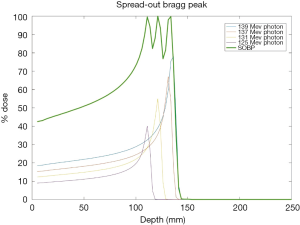

The promise of proton therapy lies heavily on the existence of a Bragg peak, a narrow region where the dose deposition peaks and falls off sharply as shown in Figure 2. Protons with higher energies deposit their maximum dose at greater depths. By accumulating weighted dose depositions over a range of proton energies, a spread-out Bragg peak (SOBP) can be obtained. This is shown in Figure 3, where the proportion of proton fluence with energies 139, 137, 131, and 125 MeV are 0.32, 0.28, 0.23 and 0.17 respectively. Using more energies between the range 125 to 137 MeV, a more uniform “flat top” depth dose can be attained. By designing proper beam entries, a very conformal dose distribution can be achieved using proton therapy, with sufficiently coverage of the clinical tumour volume (CTV), and minimal dose to the OARs which are beyond the range of the maximum energy protons (16,17). An example is as shown in Figure 4.